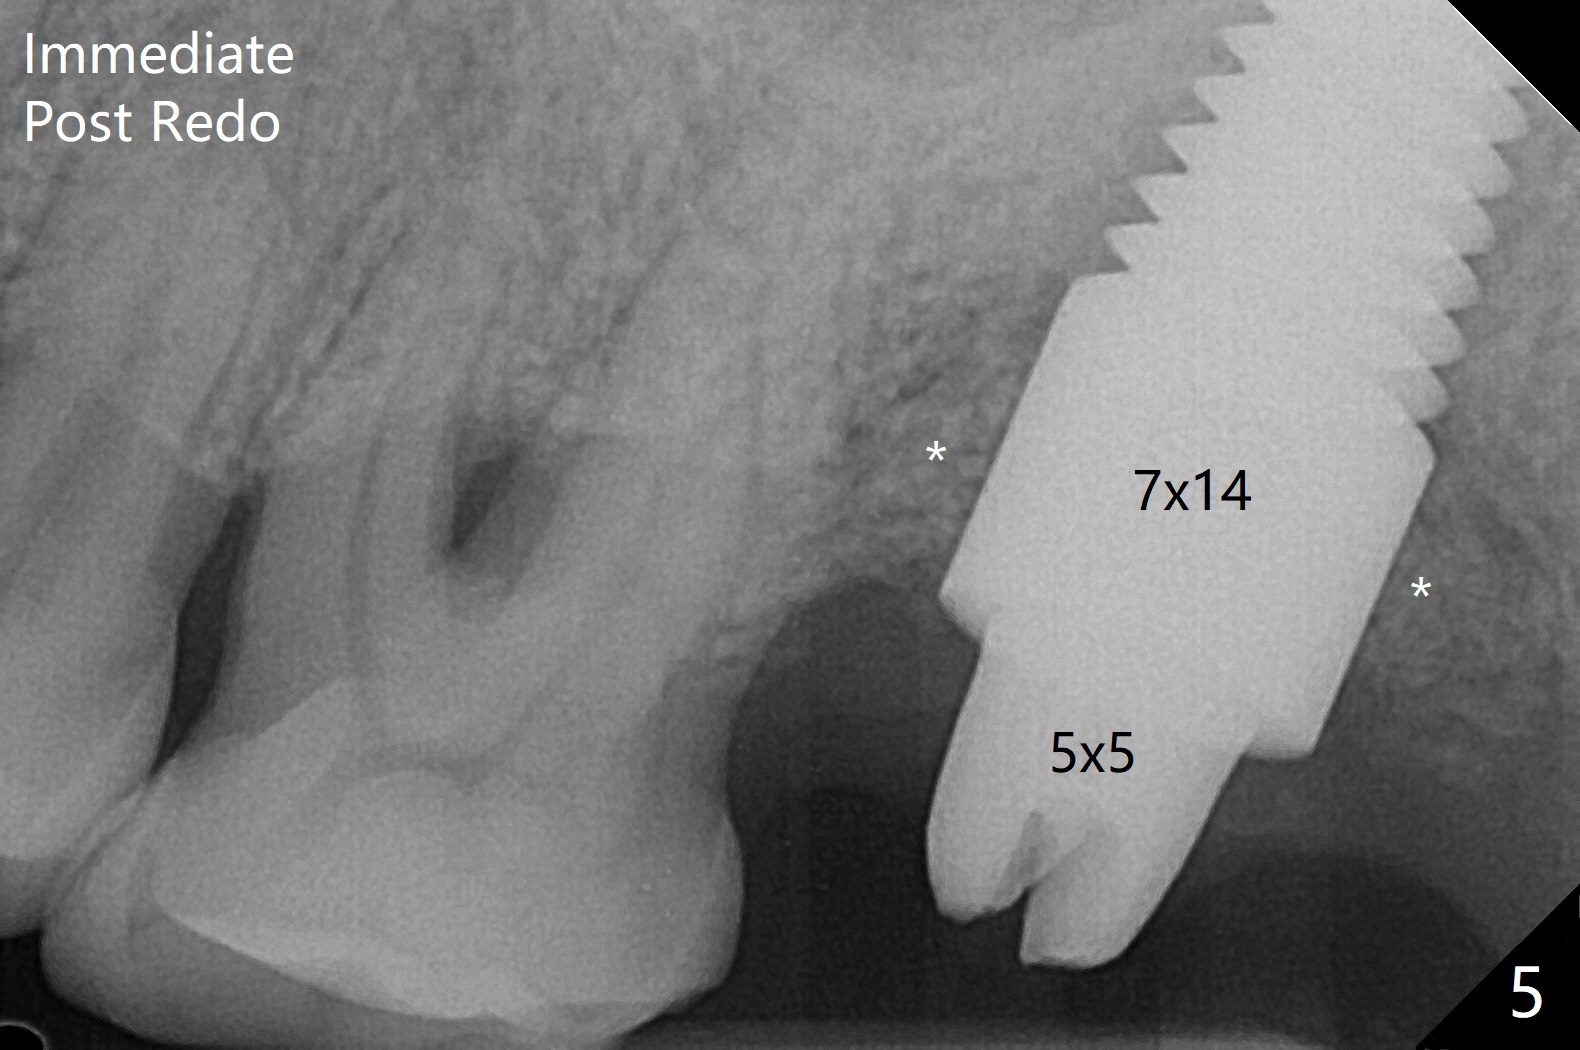

59岁男一年前因15号牙植牙周围炎去除牙冠和基台,植骨(图一:*(其实是第二次为周围炎植骨)),缝合。之后局部疼痛没有完全消失,准备再次手术(切开),如果螺纹暴露少,再次植骨。否则拔除植体(图二:黑色,手术探查的确不能挽救植体),之后有两个选择植骨(图三:灰色)或者即刻再次种植。由于原来植体比较粗(骨水平;6x12毫米),利用6(内径)/7(外径)毫米trephine drill和牙挺除去植体,留下相当大缺损(图二),植骨后(图三),位于缺损中间的骨粉(图四:棕色)可能因血供(红箭头)不足而愈合不佳。因此即刻重新种植显得有优势(图五(软组织水平植体,螺纹在自身骨(native bone)下)),让身体不必太辛苦(成骨)。放置5x5毫米基台目的是为树脂敷料提供固定点,以防PRF膜和缝线不能挽留粘性骨粉(*)。术后一个月撤除树脂敷料,伤口愈合正常(图六)。准备一个月后,制作临时牙冠。术后4个月取出5x5毫米基台,准备放置6x5毫米基台(图七),下面软组织水平植体没有疼痛或者松动,螺纹被骨粉或者再生骨质覆盖(^)。